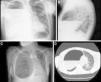

Paciente de 40 años sin antecedentes personales relevantes que consultó por disnea y fiebre. Analíticamente presentaba leucocitosis con desviación izquierda y elevación de reactantes de fase aguda. La radiografía (fig. A y B) y la TAC de tórax (fig. 1 C y D) revelaron una imagen quística con paredes calcificadas y contenido hidroaéreo, que ocupaba prácticamente todo el hemitórax derecho, provocando una atelectasia del parénquima y desplazando el mediastino contralateralmente. Se inició tratamiento con antibioterapia empírica y ante la falta de respuesta se decidió realizar el drenaje de la colección mediante toracotomía, con mejoría clínica posterior.

A y B) Radiografía simple de tórax postero-anterior y lateral que muestran lesión quística con paredes calcificadas que ocupa prácticamente la totalidad del hemitórax derecho con nivel hidroaéreo en su interior. C y D) TAC de tórax donde se objetiva que dicha imagen quística condiciona atelectasia de gran parte del parénquima pulmonar del hemitórax derecho y desplazamiento del mediastino hacia la izquierda.